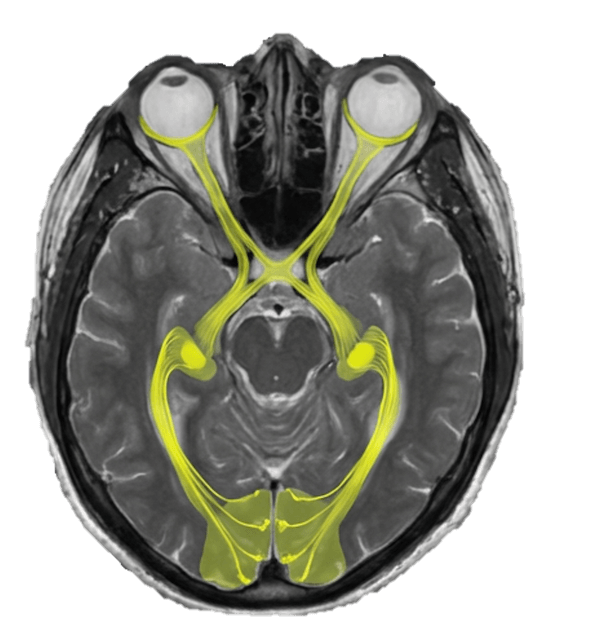

T2WIのMRI画像に視路に色をつけると以下の様になります。

解剖を見ていくと、

網膜→視神経→視交叉

視索→外側膝状体→視放線→視覚皮質

へと伝わります。

(それぞれの場所、特に外側膝状体の場所はおおよそとなります。)

実際には1スライスでこれらが見えることはありませんが、イメージとして1スライスにまとめて視路、視覚野を書き込むと以下の様なイメージになります。